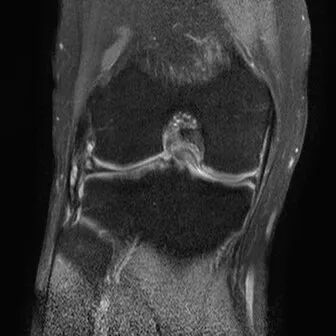

半月板纵行撕裂

1、纵行撕裂2、撕裂方向和半月板长轴方向平行3、垂直或斜行的III级高信号

(半月板纵行撕裂)